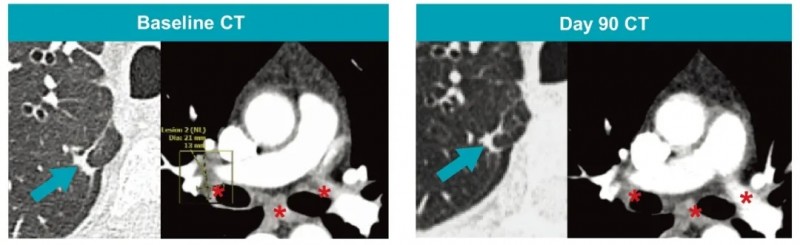

结果显示:在A2B694输注第90天,CT检查显示靶病灶全部消失(详见下图),达到RECIST1.1标准下的完全缓解(CR);第180天,经中央影像复核,正式确认这一完全缓解状态;第190天的PET-CT扫描未见疾病复发迹象。治疗后第6个月和第8个月,ctDNA检测结果持续显示KRAS G12V突变呈阴性,意味着肿瘤残留风险极低。

治疗期间仅出现一次特殊情况,在第243天患者出现孤立性脑转移,但颅外病灶仍维持完全缓解状态。针对这一情况,患者接受了地塞米松+根治性伽马刀放射外科手术联合,术后第284天复查PET-CT显示,病灶持续消失;直至治疗满12个月时,CT检查仍未发现新的病灶,疗效保持稳定。